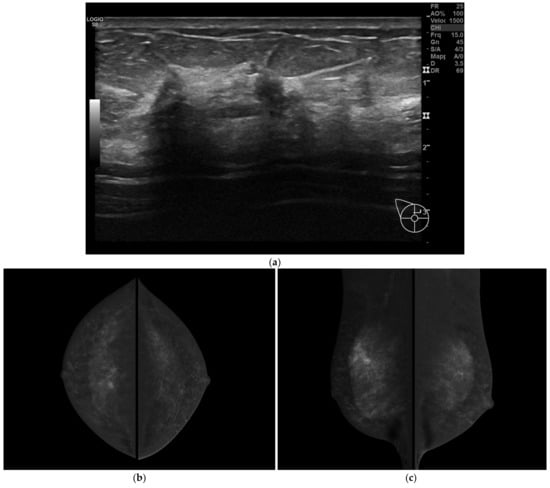

BMR missed two cases of MFMC disease (Figure 1). Sensitivity of BMR in correctly staging multifocal/multicentric disease was 94.73%. In both these cases, the target lesion was mass-like.

Figure 1.

A 47-year-old women with multifocal CLI. Patient performs mammography and ultrasound examinations for annual prevention check. (a) At ultrasound examination, two small suspicious hypoechoic lesions are visualized. Needle biopsy was performed on both lesions and invasive lobular carcinoma was diagnosed in both cases. (b) CESM CC and (c) CESM MLO views show some suspicious small-enhanced masses in the upper quadrants of the right breast suggesting a multifocal disease (T1bm N0 M0, ER 90%, PgR 5%, Ki67 20%, G2). (d) BMR axial MIP reconstruction and (e) BMR sagittal MIP reconstructions show only one small-enhanced mass lesion. In this case, BMR missed the real extent of the disease. (f,g) Postoperative specimen histology including one of the lesions previously described, Hematoxilin & Eosin stain. (f) Low power magnification showing invasive breast carcinoma with sparse, poorly cohesive neoplastic cells, associated with stromal desmoplasia (magnification 100×). (g) At higher magnification, the neoplastic cells are small sized, with scant cytoplasm and mild nuclear pleomorphism, arranged in single cells or small cords, consistent with the diagnosis of CLI (magnification 400×).

CESM missed one case of multifocal disease. Sensitivity of CESM in correctly staging multifocal/multicentric disease was 94.73%.